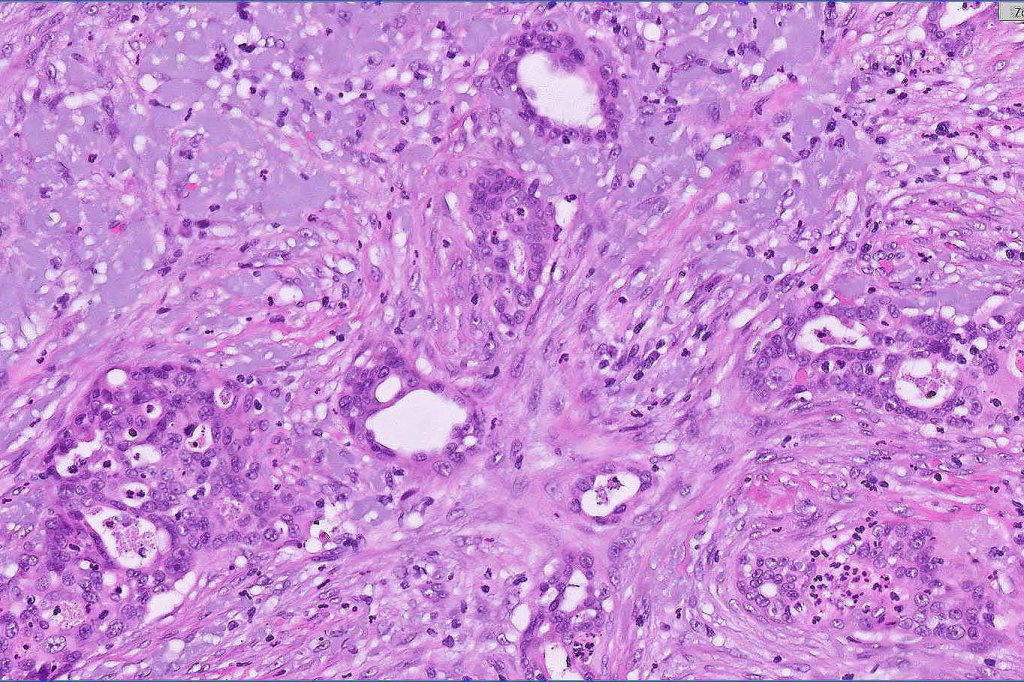

•Widely infiltrating biphasic tumor

•Adenocarcinoma in deeper reaches

•Variable pleomorphism and mitotic activity

•Deep part may show both ducts and glands

•Perineural infiltration is commonly seen